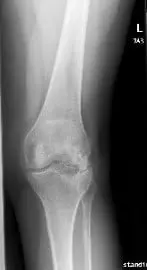

X-ray showing AP and lateral views of the left knee post removal of the lateral plateau plate.

Imaging studies revealed tricompartmental osteoarthritis, most severely affecting the medial compartment with a post-traumatic deformity of the proximal tibia.